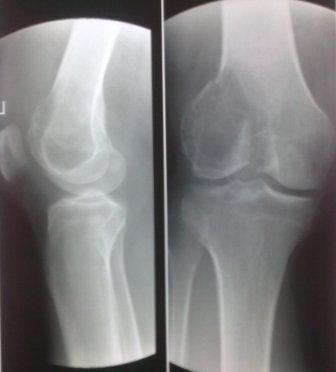

Гигантоклеточная опухоль бедренной кости

Обратился мужчина 32 лет с жалобами на боли в обл. внутреннего мышелка левого бедра. Боли беспокоят около шести месяцев, лечился дома всякими мазями и т.д. 2 неделя назад упал , и после этого боли с каждым днем усиливаются. Местно определяется резкая болезненность в обл. мышелка бедра, явление не выраженного синовита, ограничение движения в коленном суставе, мягкотканый компонент опухоли не определяется, лимфоузлы не увеличены,Р-скопия легких без патологии,клинико-биохимические анализы в пределах нормы. Гистология- гигантоклеточная опухоль.

Направил в онкологический центр, рекомендовали резекцию и ревизионное эндопротезирование коленного сустава, от которого больной отказался и опять вернулся к нам, временно фиксировали гипсовой повязкой.

Уважаемые коллеги можно ли помочь больному, т.к. на практике были, что после перелома опухоль рассосалась и переломы срослись! Или может быть аутопластика и фиксация перелома?